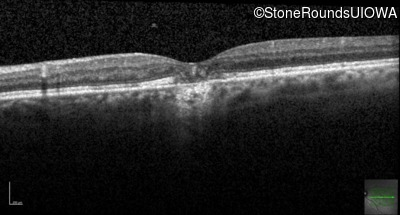

Optical Coherence Tomography - Left - 20/50 -1

Exemplar / OCT Stack

OCT Stack